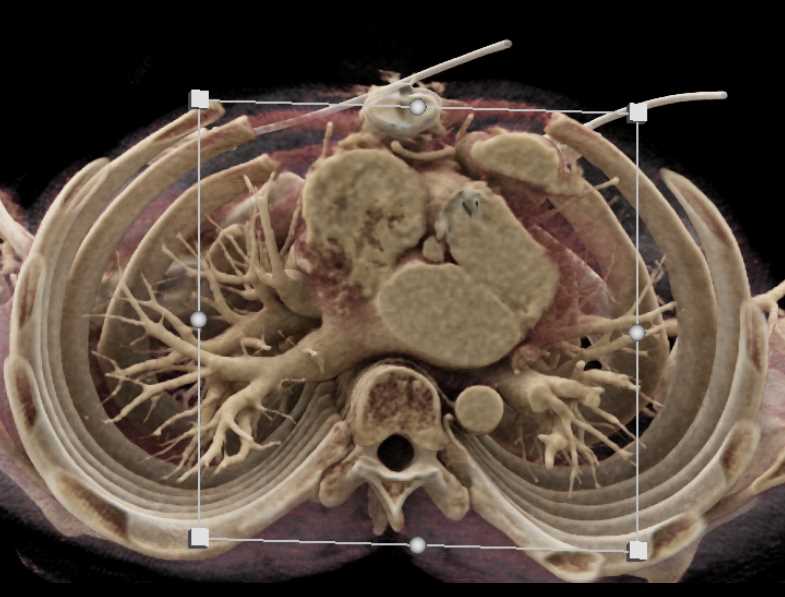

Aortic Valve Repair